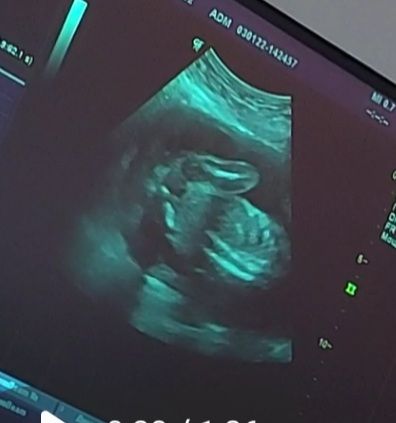

Хьюстон Прием в Благополучная беременность 4 года Узи 20 недель🌸 УЗИ, КТГ, доплер Девочки, всех с наступившим новым годом)) ну что, кого увидели на снимке?))😏 У кого хорошая интуиция?😀 Кто?) Д 48.1% М 51.9% Голосовать 52 голоса Посмотрите еще 20 записей на эту тему Отменить Ответить Доплер Не совпадение по сроку эмбриона и ПЧ Чаты Беременных Выберите чат: Январята-2026 Февралята-2026 Мартята-2026 Апрелята-2026 Майчата-2026 Июнята-2026 Июлята-2026 Августята-2026